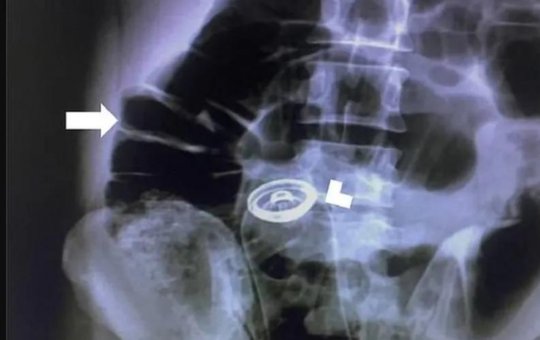

Médicos removem haltere de 2kg do ânus de homem; caso aconteceu em Manaus

Paciente de 54 anos foi a unidade de saúde com reclamações de cólica, náuseas e vômitos